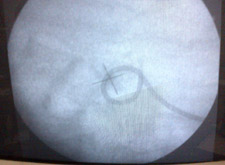

The lithotripsy procedure is done in a lithotripsy specialised centre and takes about an hour to be done. This is done on the same day care basis, usually without anaesthesia. Some analgesia and sedation may be given to allay the patient's anxiety and make him relax or go to sleep. The stone is localised with high frequency digital C-arm and the shock waves are focused on the stone. The patient may feel a tapping sensation during the procedure. If a large stone fragment remains after treatment a second sitting may be required after 7 – 10 days.